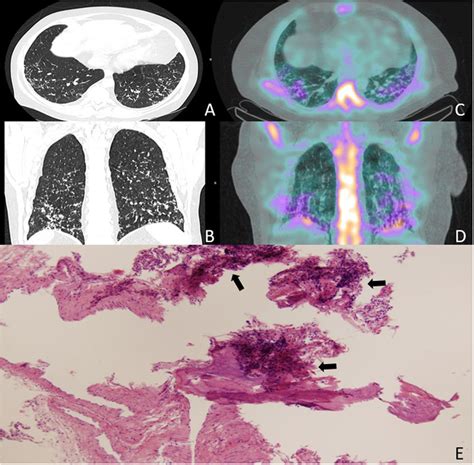

Calcification in lungs, a condition where calcium deposits form in the lung tissue, is a topic of growing interest in the medical community. This phenomenon can occur due to various underlying conditions and can have significant implications for respiratory health. Understanding the causes, symptoms, diagnosis, and treatment options for calcification in lungs is crucial for both healthcare providers and patients.

Calcification in lungs refers to the abnormal deposition of calcium salts in the lung tissue. This process can affect the lungs' structure and function, leading to various respiratory issues. The calcium deposits can form in different parts of the lung, including the alveoli, bronchi, and blood vessels. The severity and impact of calcification in lungs can vary widely depending on the underlying cause and the extent of the deposits.

• Chest X-ray: A chest X-ray can reveal the presence of calcium deposits in the lungs.

• CT Scan: A computed tomography (CT) scan provides detailed images of the lungs and can help identify the location and extent of the calcification.

• Bronchoscopy: This procedure involves inserting a thin tube with a camera into the lungs to visualize the airways and take tissue samples for biopsy.

In some cases, a biopsy may be necessary to confirm the diagnosis and determine the underlying cause of the calcification.